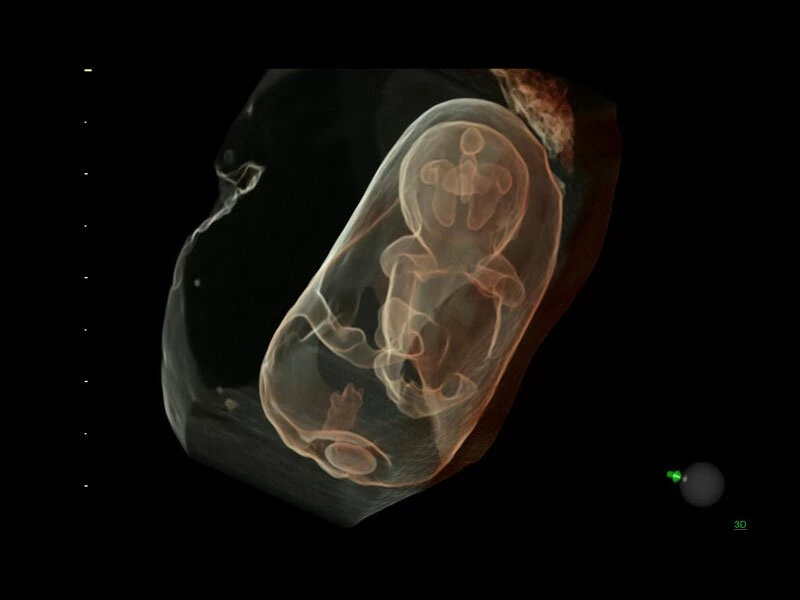

Объемное сканирование Voluson — 3D/4D вашей мечты

Объемное УЗИ на Voluson E10 — это не просто потрясающе красивая картинка, это ценный инструмент получения дополнительной информации при обследовании женщин.

Voluson E10 поддерживает инновационные технологии формирования изображений — HDlive Silhouette и HDlive Flow, которые позволяют увидеть мельчайшие детали. Алгоритм SonoRenderlive упрощает рабочий процесс и дает возможность реконструировать изображение поверхностей, определяя область перехода между тканью и жидкостью.

Инновационная технология визуализации HDlive обеспечивает получение реалистических изображений за счет эффекта объемного зрения, повышая достоверность клинической оценки. Теперь режим HDlive дополняют две новые функции:

- Технология HDlive Silhouette — задает разный уровень прозрачности, помогая выявлять контуры внутренних структур и точнее оценивать состояние плода в первом триместре.

- SonoRenderlive

- Улучшает объемную визуализацию за счет автоматического определения линии начала реконструкции при изображении поверхностей. При исследовании в режиме 4D функция SonoRenderlive непрерывно обновляет положение исходной линии с учетом движений плода.

- Режим 3D SonoRenderLive – инновационная система, позволяющая определять четкие границы лица и конечностей плода в объеме, избавляясь при этом от лишних артефактов, шума и помех.